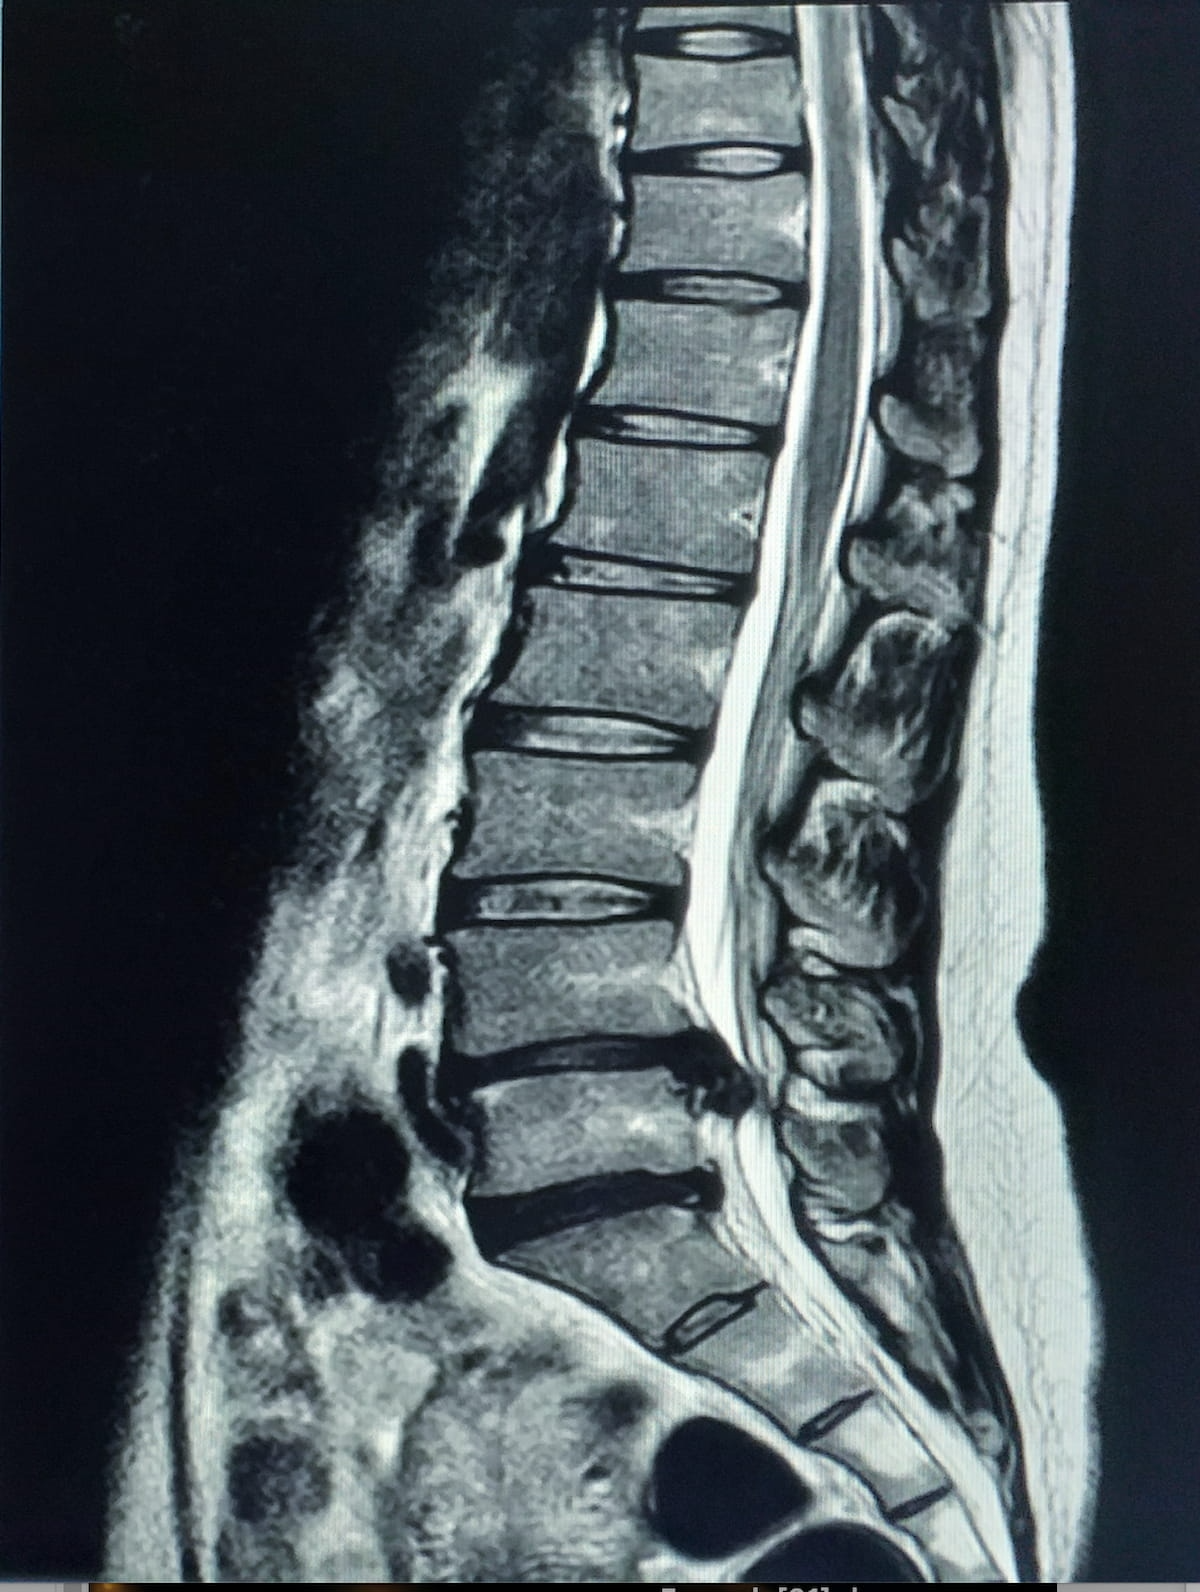

FDA Clears AI Software for Lumbar Spine MRI Analysis

The MSKai software provides AI-powered segmentation, labeling, and measurement tools for assessment of T2-weighted MRIs of the lumbar spine.

The Food and Drug Administration (FDA) has granted 510(k) clearance for MSKai software, which offers a variety of adjunctive artificial intelligence (AI) tools for evaluating lumbar spine magnetic resonance imaging (MRI).

Through assessment of T2-weighted MRI scans of the lumbar spine,